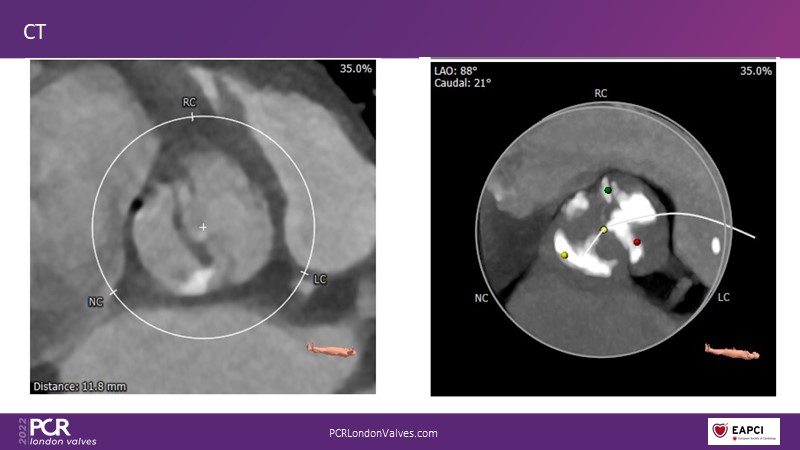

This session addresses three important topics that impact post-procedural and long-term outcomes after performing TAVI: the impact of permanent pacemaker rates and paravalvular leak, the importance of neo-commissural alignment, and the role of cerebral embolic protection.

- To appreciate the potential importance of neo-commissural alignment